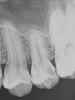

Каплан Опубликовано 5 октября, 2012 Поделиться Опубликовано 5 октября, 2012 немного из диагностики...снимков с полости рта нет, но на 26 вообще не видно, а вот на 27 "кариус корня".... http://imageshack.us/a/img826/7051/60980810.jpg Uploaded with ImageShack.us вот так вот тоже бывает... в анамнезе была пародонтология, на верхней челюсти, квадрант не помнит... теоретически можно это подвести под причину. но. на нижней челюсти на резцах-клыках тоже есть аналогичные поражения... так что...как-то так... клык сегодня депульпировали и закомпозитили...эти 3 направили к хирургу.как-то так... Ссылка на комментарий

Stomart Опубликовано 5 октября, 2012 Поделиться Опубликовано 5 октября, 2012 Лечил подобное сегодня у своей знакомой. Дистальная полость в 27 зубе, объективно не видимая, по 2 классу химкомпозитная пломба лежащая на десне -> атрофия дены -> попадание пищи между зубами -> кариус корня. Честно говоря если бы не знакомая отправил бы на удаление, а так пришлось продлить жизнь зубу на год-два, тем более, что имплант она не потянет финансово. Ссылка на комментарий